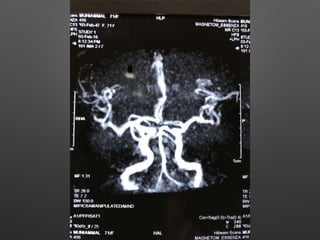

HOPI • Patient wasapparently normal till 5pm 3/2/18, started behaving abnormally like half dressed, with carrying comb and want to go temple, with irrelevant talks. • Relatives observed paucity of left Upper and lower limb, thinking of stroke - took her to near by hospital • Asked for imaging - after imaging she developed 2 episodes of left sided jerky movements of both UL & LL with twitching over the face - lasted for 1-2 min, treated with sedative , Inj. insulin for high CBG - 495 mg/dl and referred here for further management.

Provisional Diagnosis • ?Acuteischemic stroke - left hemiparesis with focal seizures • ? Hyperglycemic encephalopathy • ? Viral encephalitis

Investigations • HB- 14.1gm%- 12.2 • WBC- 15990cells/cumm - 10770, -P 83%, L-9%,M-7% • Platelets - 3.3lakhs - 2.8 • ESR- 63mm/hr • RBS - 267 mg/dl • CUE - N • RFT - N • LFT - N • S.Na - 137, k+ - 3.9, Mg- 2.1, Ca- 9.1, Ph- 3.5, Ammonia- 0.29

• ECG -N • 2DEcho- N • U/S - Abd- Gr I Fatty liver changes